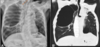

13

Q

A

Consolidación alveolar